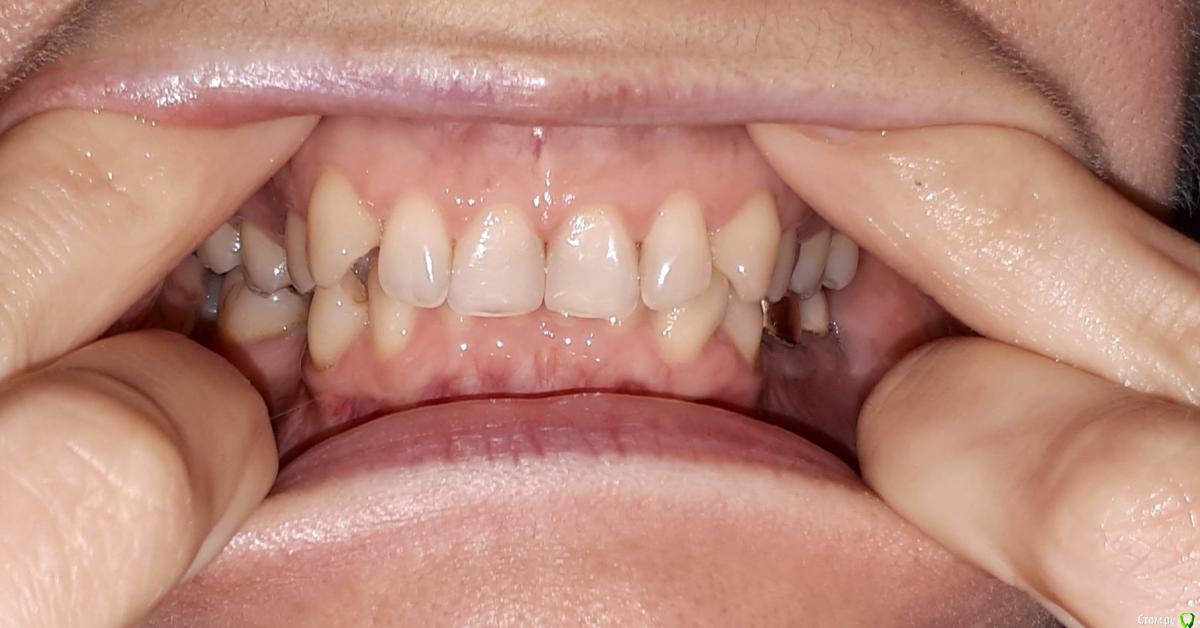

Thunder Опубликовано 17 октября, 2019 Поделиться Опубликовано 17 октября, 2019 Приветствую всехПрошу быть снисходительными: рассказываю свою историю первый раз, заранее приношу извинения за возможный сумбур и некорректность в использовании проф. терминологии. Мне 40 лет. У меня:-глубокий прикус-скученность зубов во фронтальном отделе в/ч и н/ч; -короткая уздечка верхней губы, -мелкое преддверие полости рта, -тонкий биотип пародонта; -проблемы с суставом (левым), который периодически дает о себе знать: обычно ограничивается щелканьем, но пару раз и воспалялся (боли, рот с трудом открывался, особенно по утрам). Ничего, кроме местных мазей на сустав не наносила и особенно им никогда не занималась.- В этом году мне поставили диагноз полиостеоартроз (болят суставы нижних конечностей). - постепенно появился перекос челюсти влево, видно уже невооруженным глазом (возможно, после удаления верхней левой восьмерки)Прикус никогда не исправляла, по разным причинам, в том числе, потому что не хотела ставить брекеты. И сейчас не хочу (комплексы). Комплексы от некрасивой улыбки тоже были, но к своей внешности за столько лет уже привыкла (и смирилась), кроме того она мне совершенно не мешала жить. Однако!В последние годы вынесла основную мысль от стоматологов – мои суставы разрушаются (в большей степени левый), происходит это из-за моего прикуса, который срочно надо исправлять. Эстетика лица для меня – вторична. Вся работа над зубами должна проводиться именно для сохранения сустава (ну и чтобы зубы не потерять).В начале 2019 г. были сделаны ОПТГ, КТ и ТРГ. Есть еще зонография ВНЧС (правда от 2017г.) // не поняла, как КТ подгрузить, но есть описание врача Пикассо. Если надо будет, просто загружу как текст. Остальные фото, надеюсь, подгрузить получится// По КТ ортодонт, к которому я, наконец, обратилась, выявил «убыль костной ткани межальвеолярных гребней и вестибулооральных стенок по смешаному типу до 2,0 мм.» (кортикальная пластинка истончена по вестибулярной поверхности на передних зубах (в/ч зубы 1.2-1.1,2.1-2.4; н/ч зубы 3.1.-3.4, 4.1-4.5) до 0,1 мм). Мой ортодонт (лечение на капах) сказала, что риск потерять зубы при лечении на капах – 50/50, при лечении на брекетах – и того выше. После этого, конечно, я ушла.Стала искать дальше. Каждый раз мнения разнились:1 вариант: можно капами исправить прикус, но крайне осторожно2 вариант: только (!) брекеты. Тема потери зубов обходится стороной или уверяют, чтобы зубы останутся на месте засчет длинных корней. Если я не поставлю брекеты притом срочно – через несколько лет я потеряю все зубы, и мне придется тратиться на съемные протезы3 вариант: зубы вообще не трогать, просто всю жизнь носить каппу, помогающую моему суставу.4 вариант (стоит особняком): суставная каппа на нижнюю челюсть + одновременно аппарат ALF на верхнюю.Почему ALF? потому что из всех ортодонтических аппаратов для исправления прикуса этот – самый щадящий. Брекеты категорически не рекомендованы, потому что самые агрессивные по воздействию, каппы дороже + отмели из-за сустава: его было удобнее лечить параллельно с ALF. Смысл использования у меня ALF (как поняла) не столько в расширении челюсти, сколь в изменении наклона верхних зубов, которые не «пускают» нижнюю челюсть вперед. Мои зубы при этом не выпадут, а врастут в кость, изменив угол наклона.Второй этап – ALF или инвизилайн на нижнюю челюсть; и для возобновления смыкания боковых зубов – пломбы или коронки (эта часть смутила). В данном лечебном плане было прекрасно все, кроме моей неуверенности в достаточной квалификации врача. У меня сложилось впечатление, что для врача эта методика как бы.. далеко не основная. Она использует ALF просто как один из вариантов ортодонтических аппаратов (наряду с брекетами и пр.), а я так понимаю, у ALF философия немного другая (тесная связь с осанкой, остеопатией и пр.) – хотя могу и ошибаться. И в принципе эта методика новая, не особенно опробованная в России, отзывов нет, особенного опыта у врачей тоже. Страшно.Мучают вопросы, на которые здесь, возможно, получу ответы:1. мне были рекомендованы френулопластика на в/ч, вестибулопластика на н/ч. На сколько это необходимо в моем случае и что будет, если я их делать не буду2. последний ортодонт мне пригрозил полной потерей зубов через некоторое время, если не поставлю брекеты. Она была единственной, кто мне озвучил подобные последствия. Альтернативой исправления прикуса действительно будет только полное протезирование через несколько лет? если я не буду делать ничего, то чем, на самом деле это грозит? 3. какие ортодонтические аппараты при моих лежащих на поверхности зубах мне рекомендованы? не потеряю ли я зубы в результате лечения?страшно! 4. ваше мнение об ALF!5. в продолжение 3-го вопроса: возможно ли (при варианте «брекеты») мое лечение на лингвальных брекетах? можно в комбинированном варианте: в/ч лингвальные + н/ч обычные вестибулярные? готова терпеть все неудобства с ними связанные. но "внешние" брекеты не хочу, не могу психологически заставить себя носить. 6. так понимаю, что, учитывая мой диагноз полиостеоартроз и проблемы с суставом – о нем я тоже не должна забывать. И должна лечиться у врача, который эти проблемы (и все остальные) умеет учитывать. В общем, хотелось бы услышать ваши рекомендации по поводу врача в Москве. Можно в личку Заранее спасибо! Ссылка на комментарий

krokomot Опубликовано 17 октября, 2019 Поделиться Опубликовано 17 октября, 2019 сделайте фото передних зубов с десной со вспышкой, попросите кого-нибудь. зубы вы точно не потеряете, но проблемы есть. Ссылка на комментарий

krokomot Опубликовано 21 октября, 2019 Поделиться Опубликовано 21 октября, 2019 Не вижу проблем использовать бреккеты. Атрофии десны нет. Ставте бреккеты и лечите свой прикус. Ссылка на комментарий